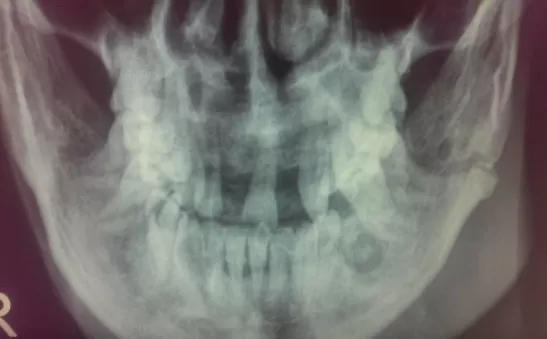

Больно открывать челюсть после